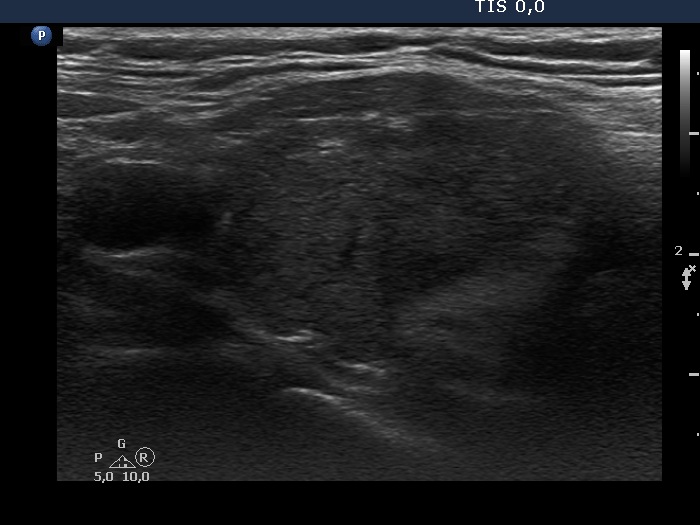

Consecutive patients with the final diagnosis of Hashimoto's thyroiditis - case 47 (449) (ultrasonographic picture 5)

Left lobe, longitudinal view.